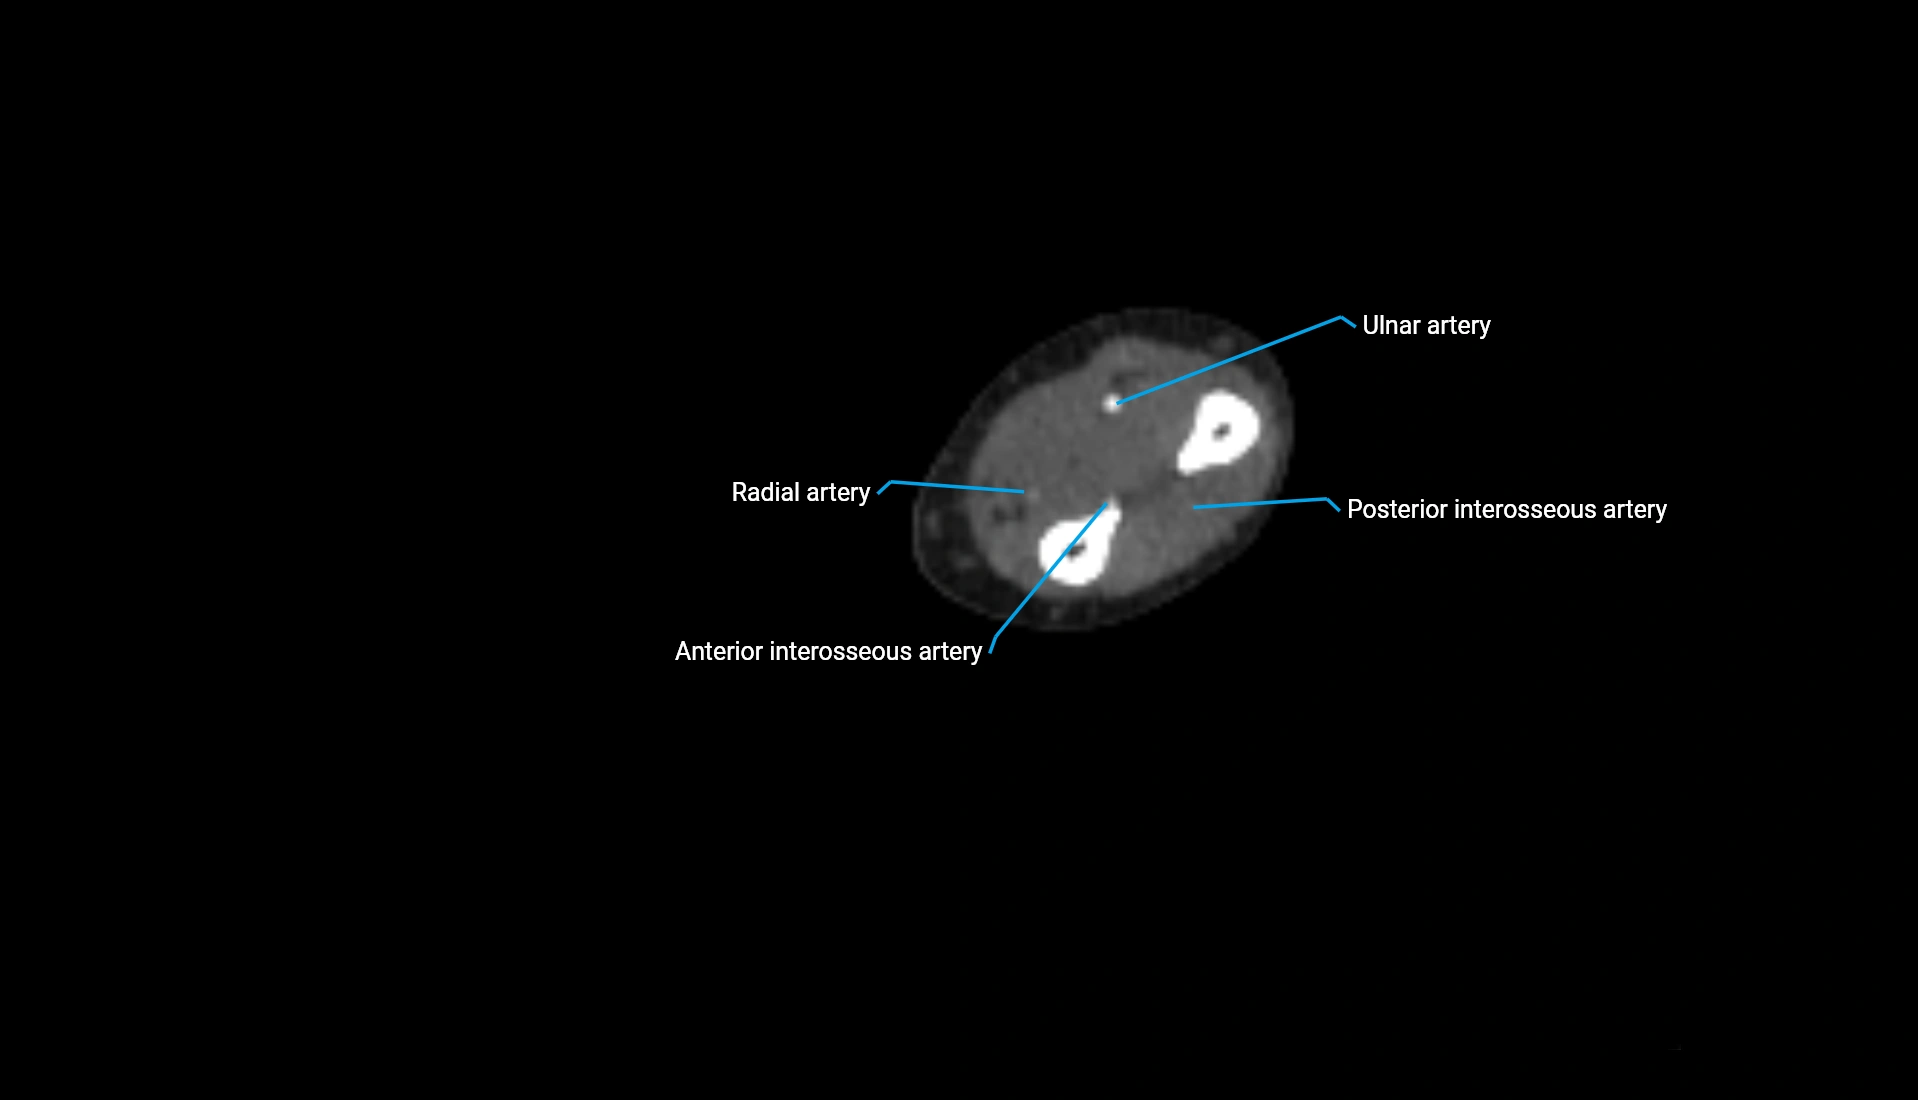

Post-Contrast CT:

• Bone: No enhancement

• Joint capsule and synovium: Mild enhancement outlining the joint

• Improves contrast between soft tissues and bony margins

• Useful in detecting subtle joint abnormalities or postoperative changes